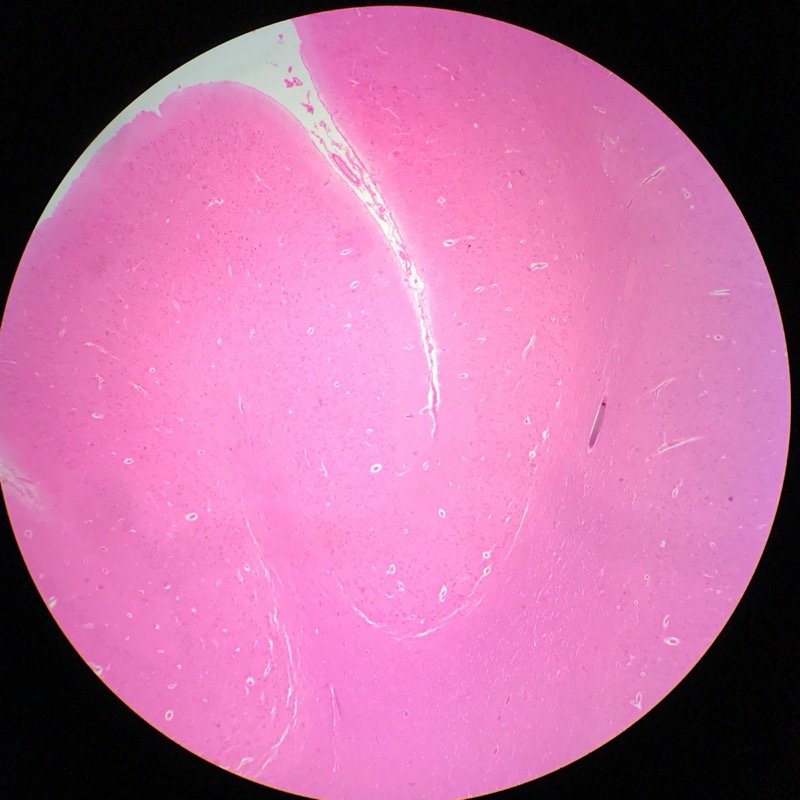

| 1:8:5 | Medulla Spinalis Galiomycin/Azan | ![]() ![]() ![]() ![]() |

| 1:8:6 | Medulla spinalis, silverfärning | ![]() ![]() ![]() ![]() ![]() ![]() |